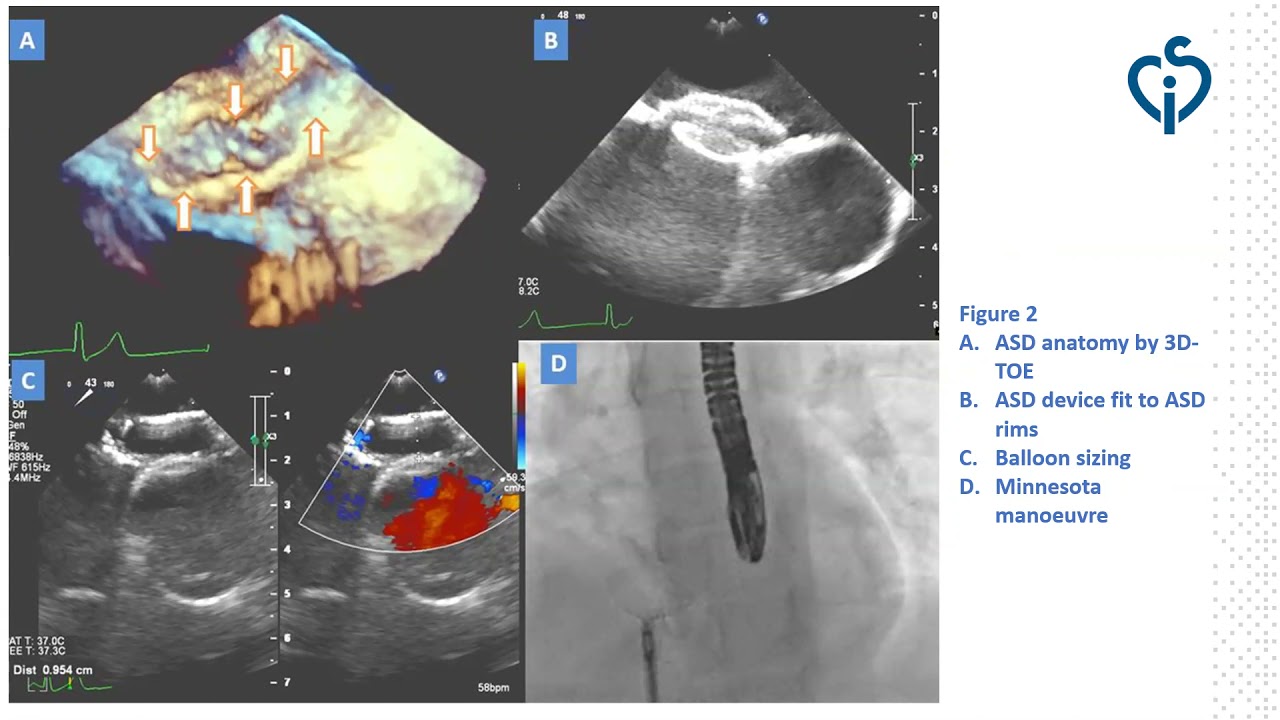

Minnesota manoeuvre: is it enough to ensure ASD device stability?

By: Charalampos Kotidis, University Hospitals of Leicester, Leicester, UK